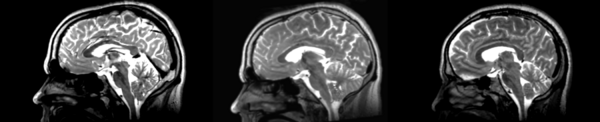

- 01053-t2 -> 01031-t2 = Result. All the images shown have the moving image on the left, the resultant image in the middle, and the target image on the right.

Rigid

01053>01031rigid.png = not bad... different brains of different sizes, but seem to be aligned in the ventricles so output seems okay. output slightly blurry. bad initial leveling displays.

Linear

01053>01031linear.png = not bad... different brains of different sizes, but seem to be aligned in the ventricles so output seems okay.output slightly blurry. bad initial leveling displays.

Affine

01053>01031_affine.png = looks good in terms of size. odd warping of frontal lobe and cerebellum area, but otherwise good coregistration.

B-spline

01053>01031_bspline.png = looks good in terms of size. odd warping of frontal/temporal lobe and cerebellum area, but otherwise good coregistration.

Diffeomorphic Demons

01053>01031_demons.png = 10 minutes. Window/leveling initially off. Otherwise, it looks really good. Not much distortion.